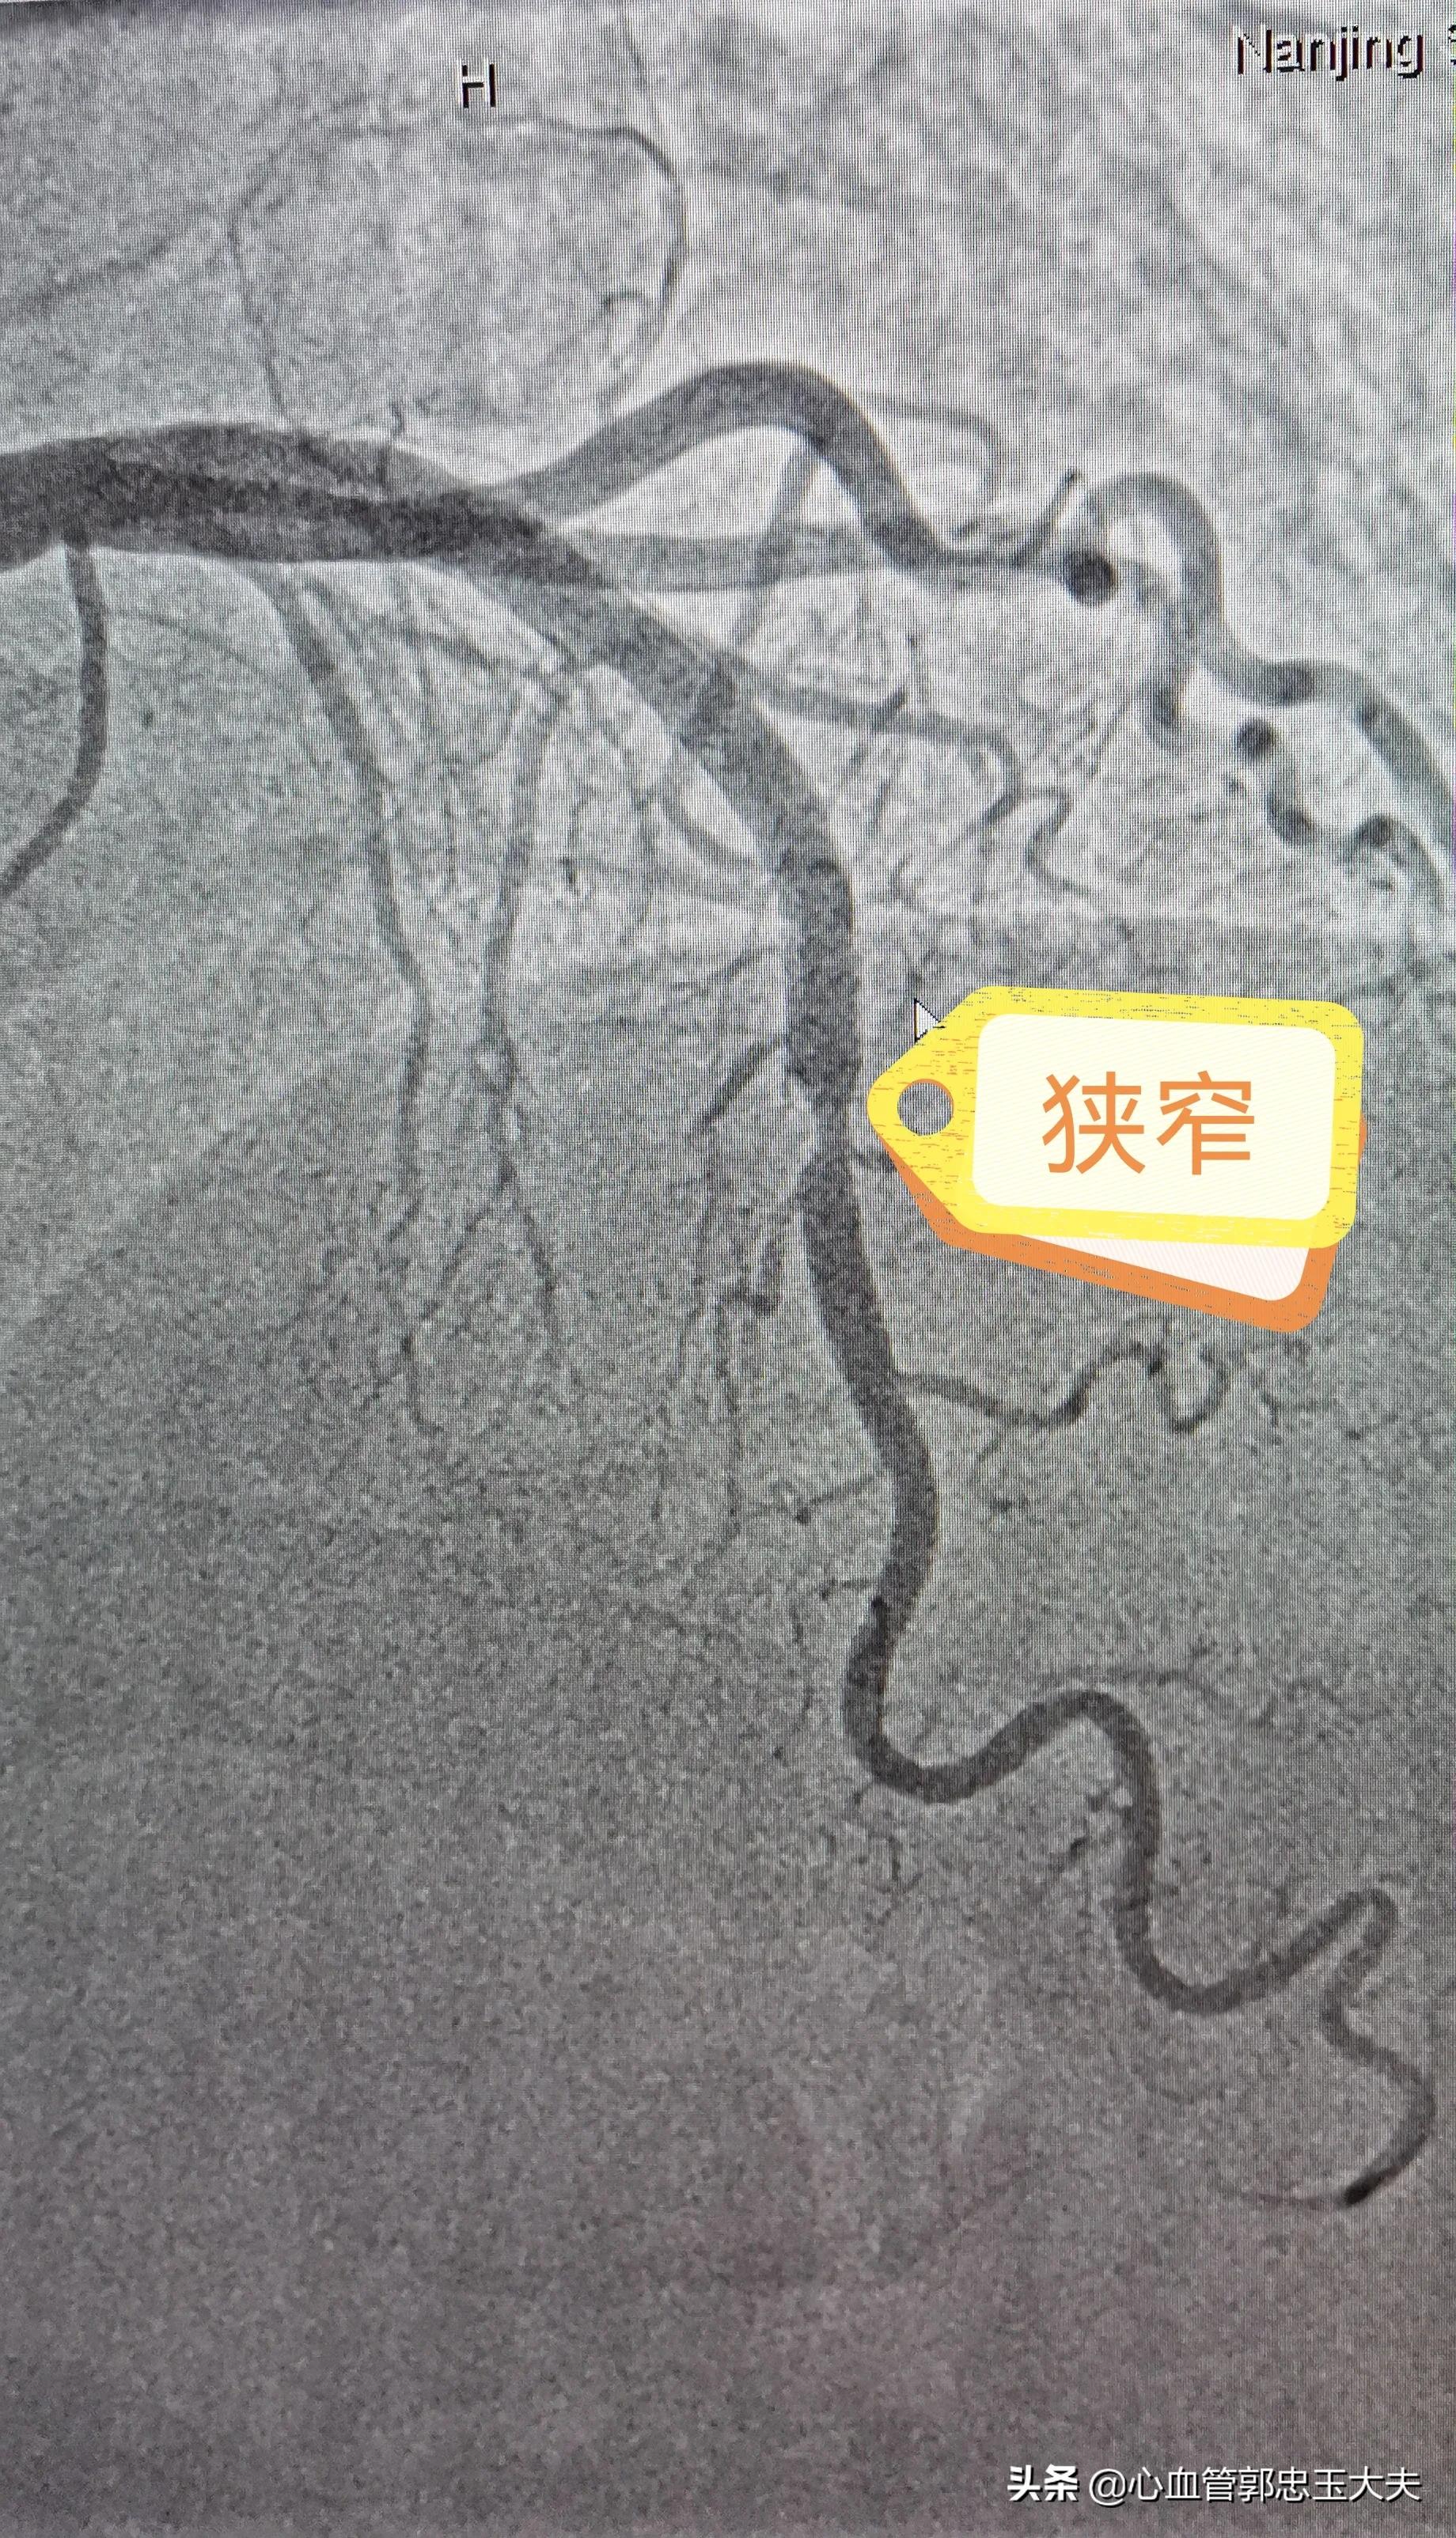

由于患者已经做过一次支架,去年5月份复查过一次造影血管是“好的”,对再次造影很*制抵**,考虑到 典型的劳力性心绞痛症状及心电图缺血改变 ,还是 决定冠脉造影检查 。经过与本人及家属反复沟通,终于同意造影。术中造影示:前降支近段到中远段可见支架影,支架内血流顺畅, 支架内远端及边缘血管80%狭窄 ,按照 支架内再狭窄定义:支架内及边缘5mm内血管再次50%以上狭窄 。考虑 支架内再狭窄 。患者及家属拒绝再次植入支架,故选用药物球囊扩张,术后狭窄消失,未见夹层形成。手术圆满结束。

支架内远端及边缘外血管狭窄80%